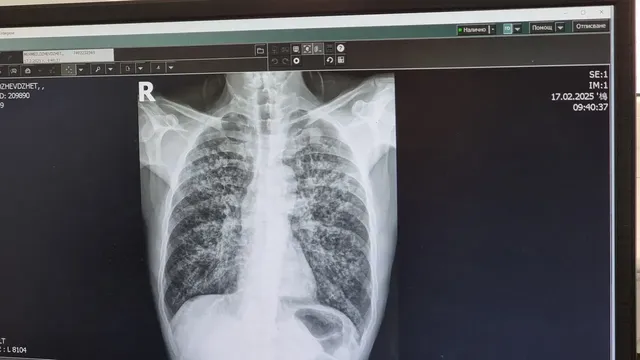

Безплатни консултации за туберкулоза в столицата до 27 март

Седмица на отворените врати в СРЗИ предлага информация, прегледи и насоки за превенция до 27 март